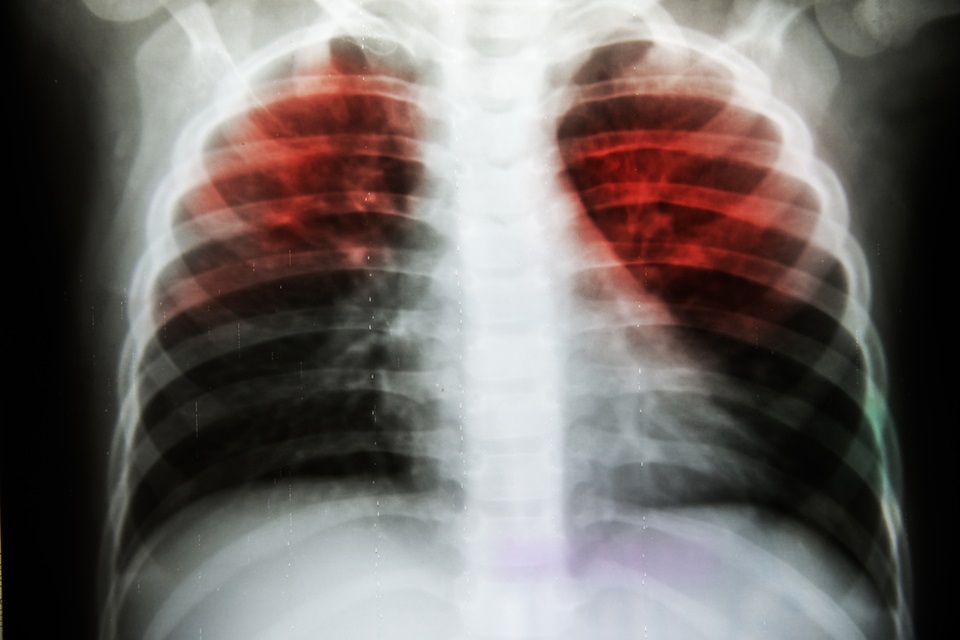

Researchers working to improve mental health of tuberculosis patients worldwide

A Keele University professor is co-leading a research team aiming to improve mental health in tuberculosis (TB) patients by developing a new psychological treatment.

Tuberculosis is still a significant healthcare problem around the world and is the 10th most common cause of death worldwide, while almost half of TB patients also report suffering from depression as well.